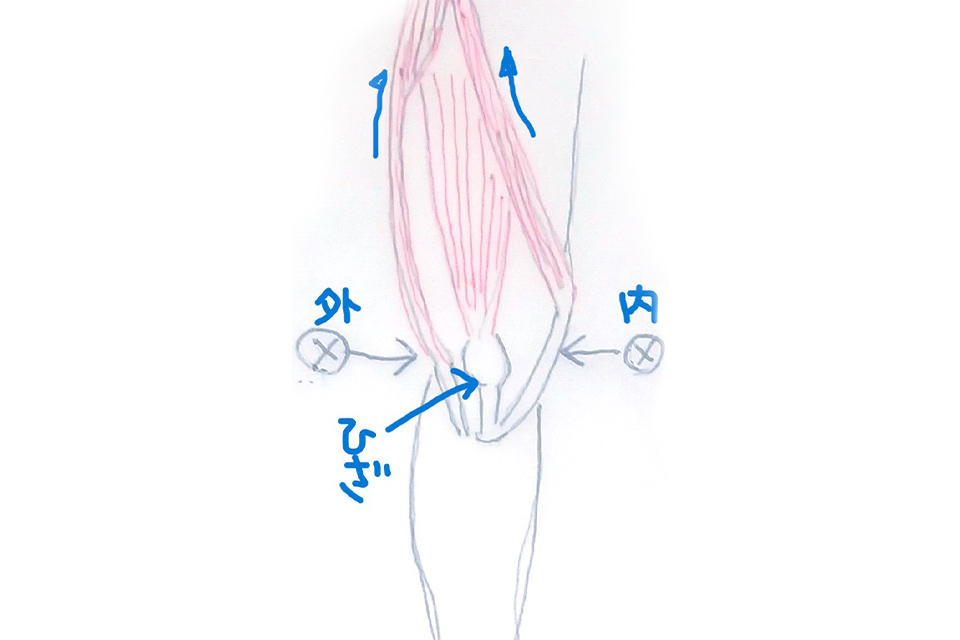

関節痛・神経痛の施術なら

新小岩ひかる接骨院にお任せ

新橋〜松戸・新小岩の整形外科のリハビリ室を長年経験した実績がありますので

関節痛と神経痛には特に自信を持って施術しています。

痛みの原因を探り出し、施術することで完治への近道につながります。

マッサージでごまかすようなことは一切しません。